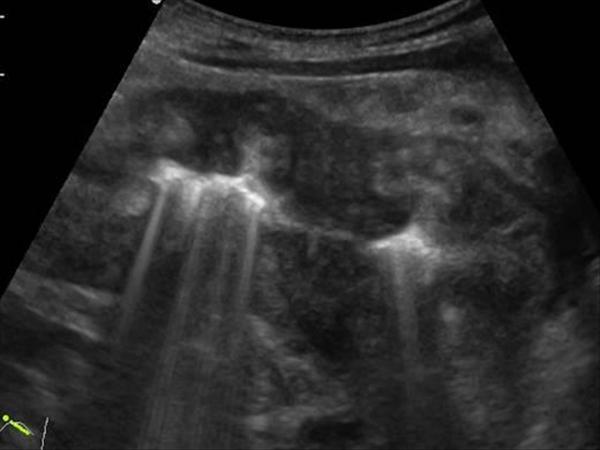

U dạ dày

» Thông tin: Nam giới – 41 tuổi.

» Lâm sàng: Đau thượng vị / Sút cân.